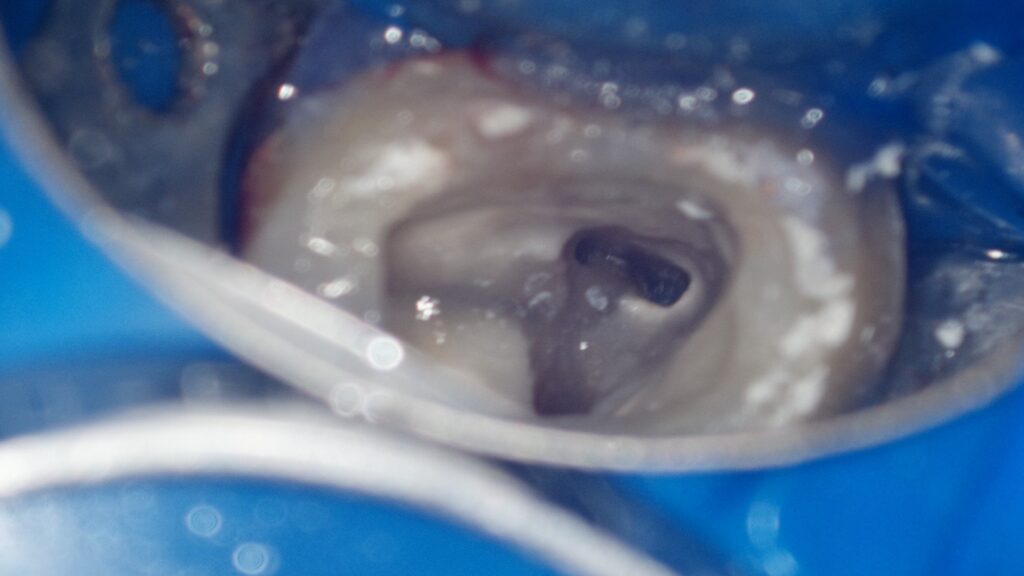

根の中をマイクロスコープで確認し、歯根の破折は確認できなかったため、精密根管治療により歯を保存することとしました。

実際の治療中のマイクロスコープで確認した画像です。

奥歯の場合、いくつかの根管に分かれているため、すべての根管を丁寧に清掃していきます。

マイクロスコープを用いて高倍率で確認すると、1本の根管と思われていた部分が、途中から枝分かれして2本となっていました。

根管の形は全ての歯で異なっており、一つとして同じものは存在しません。CT画像と実際のマイクロスコープの画像を重ね合わせることで、全ての根管を清掃し、治療の成功率を上げることが可能となります。

今回は根の先が外部吸収により破壊されていました。こういった場合、通常の根管充填では緊密に充填することが難しく、バイオセラミック単体での根管充填を行うことで、成功率が高くなると報告されています。